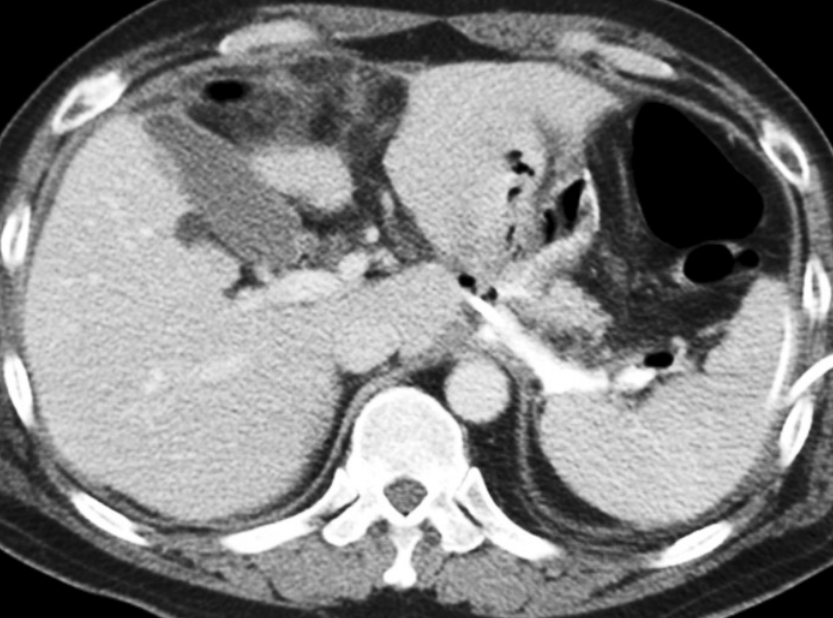

수술 후 10일 째에 시행한 전산화단층촬영에서 식도 소장문합부위 하방과 췌장후방구역, 십이지장 절단 끝의 앞쪽으로 구획화된 액체 저류가 있고 오른 결장주위 공간으로도 액체저류가 있음. 해당 액체 저류들은 미약한 조영 증강이 동반되어 있어 감염된 액체 저류의 가능성이 있고, 이와 같은 소견은 식도소장문합부위 또는 십이지장 절단 끝의 누출 가능성을 시사하는 소견임 (Fig. 1).

Fig. 1

A-B. Contrast-enhanced axial CT scan shows localized fluid collection in extent of inferior aspect of esophagojejunostomy site, retropancreatic area, anterior aspect of duodenal stump, and right paracolic gutter.